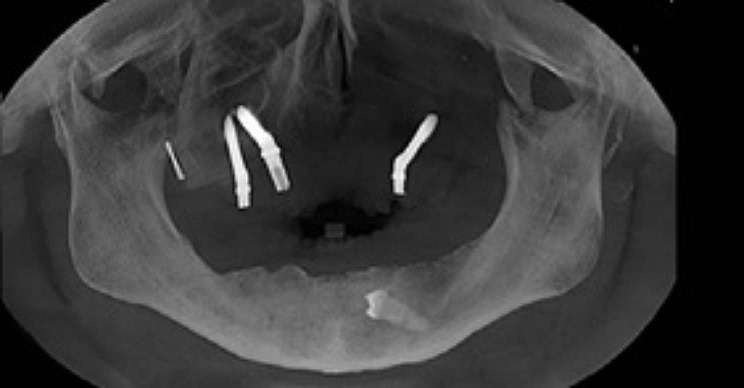

Materials and methods: The study included 16 patients who underwent prosthetic rehabilitation using a zygomatic implant after maxillectomy period from 2021 to 2023. After the tumor was removed, immediate surgical obturators were placed. Main prosthetic rehabilitation was performed 6-12 months after tumor removal, but before that, a temporary obturator was made and used. Six-twelve months after tumor resection, 1-4 zygomatic implants were inserted into the zygomatic bone unilaterally or bilaterally. A total of 42 zygomatic implants were installed, 2 of which were unsuccessful and were removed in 1 patient. The implants were placed using the surgical guide, which was planned and prepared digitally.